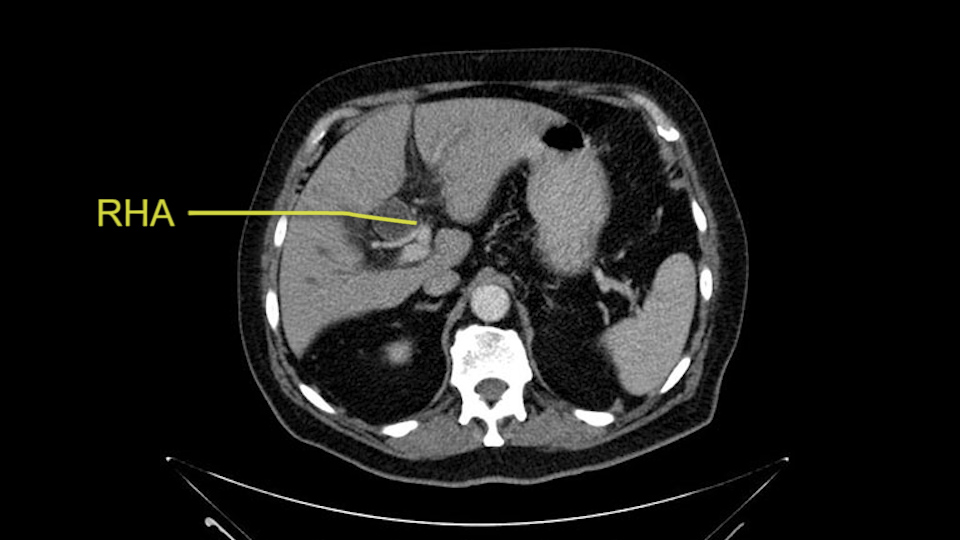

Then you look for anomalies. The one you worry about the most doing a Whipple is a replaced or aberrant right hepatic artery coming off the SMA at its origin. So again, find the SMA. You can find it because the renal vein goes through it. Follow it up, up-up-up. Nothing coming off of there that I can see here. Nothing coming off of it, nothing coming off of it and just to confirm it, look at the celiac trfurcation. There’s the celiac, there’s the bifurcation, there's the splenic artery, hepatic artery. Make sure there’s a right, which there is here. The right usually goes under the bile duct: important when you’re going around the bile duct to do a Whipple. A replaced right goes under the portal vein and the bile duct way over here on the right. That’s about it.

The second point about the vascular anatomy-, is to again look for right hepatic arteries in the hilum, coming from the superior mesenteric artery by palpating-through the Winslow Hiatus. Usually we will check for a pulse in the posterior aspect of the hepatic hilum, where a right hepatic artery should not usually be found. In this case, the precaution is to avoid an accidental ligation of the right hepatic artery that might jeopardize perfusion of the right lobe, or if there is a completely replaced hepatic artery that can put the liver circulation at risk.

I am a believer in pylorus preservation. And in this case I see no reason why that wouldn't be possible. Mobilize the duodenum, divide the gastroepiploic vessels and divide the duodenum. I try to divide it with a linear stapler about four centimeters from the pylorus to have adequate length for my GI anastomosis. This facilitates exposure of the head neck of the pancreas. I find the gastroduodenal artery. This patient has normal arterial anatomy. Always on every preoperative CT scan I look to see if there is a replaced right hepatic. In this case I did not see one. Regardless of how confident I am I always look carefully for variant anatomy. I always do a clamp test on the GDA before ligation. I doubly ligate the GDA with not just a tie but a suture ligature because of the risk of GDA blowout in patients with a leak.